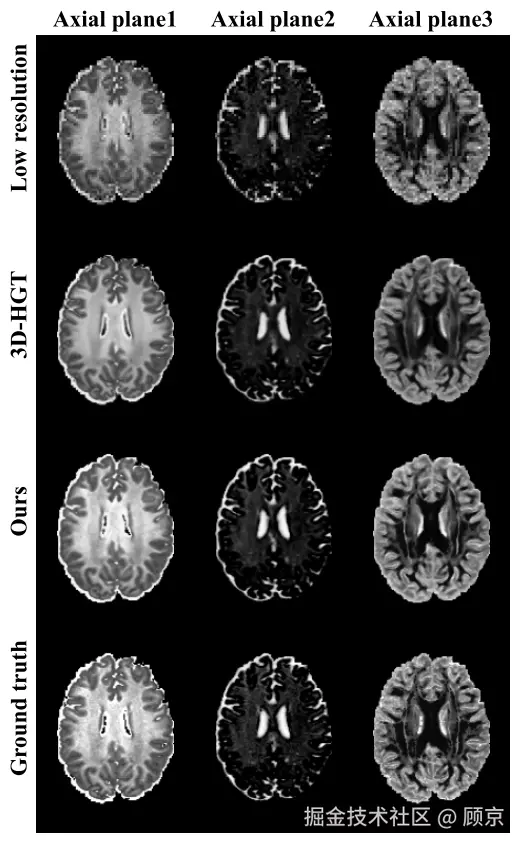

实验结果

实验结果.png

图11 生成高分NOODI结果

如图11所示,相比低分NODDI,我们生成的结果显然具有更高的质量,其PSNR25.39SSIM达到了0.931.